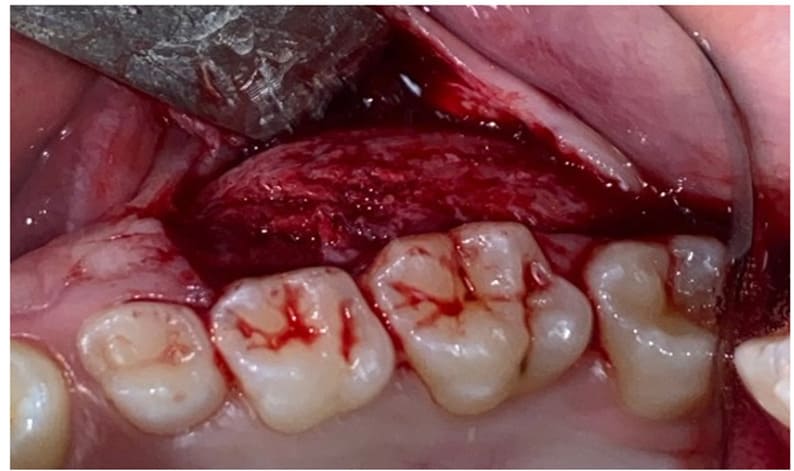

In Case 1, under local anesthesia (2% Mepivacaine Hydrochloride with 1:100000 adrenaline), a mucoperiosteal flap was raised (Fig. 3), fully exposing the fibro-osseous tissue. An incisional biopsy was then performed (Fig. 4), obtaining a sample measuring 2 cm x 0.6 cm x 0.3 cm (Fig. 5).

Figure3: Elevation of the flap and exposition of the lesion.

Figure 4: Osteotomy performed with Piezosurgery technique